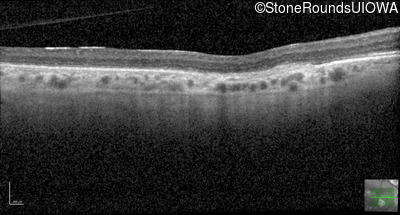

Optical Coherence Tomography - Right - 20/100

Exemplar / OCT Stack